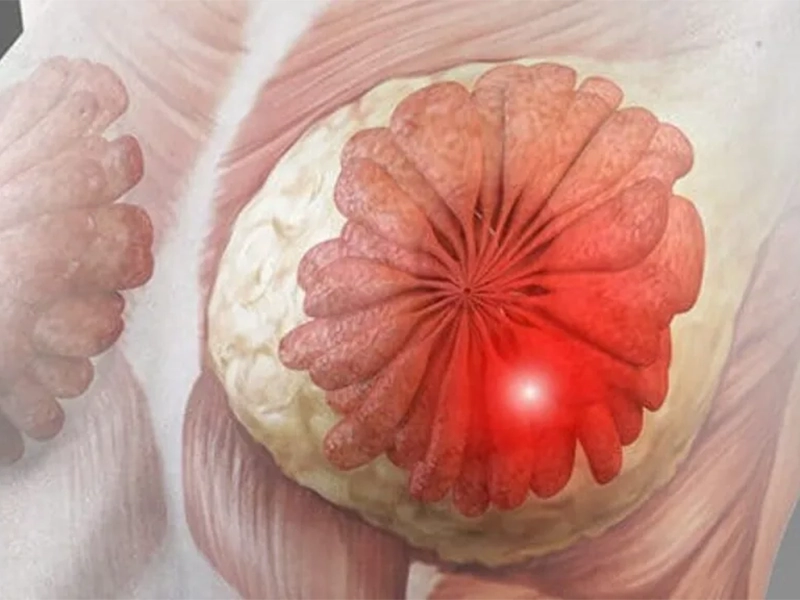

سرطان التهابی سینه (Inflammatory Breast Cancer یا سرطان التهابی پستان) یکی از نادرترین و در عین حال تهاجمیترین انواع سرطان